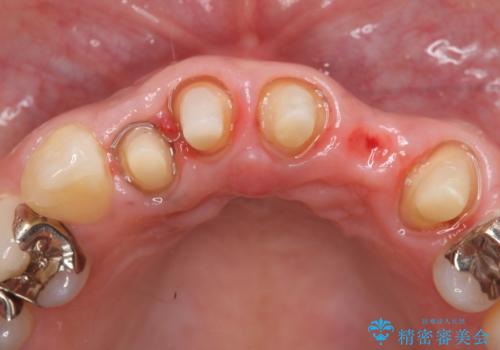

- 昔入れた被せ物と歯茎の間の隙間が気になると来院された方の症例です。

右上1、2番目の歯と左上1、2、3、番目の歯のブリッジを除去し、オールセラミッククラウンによる補綴を行うことで見た目を改善しました。